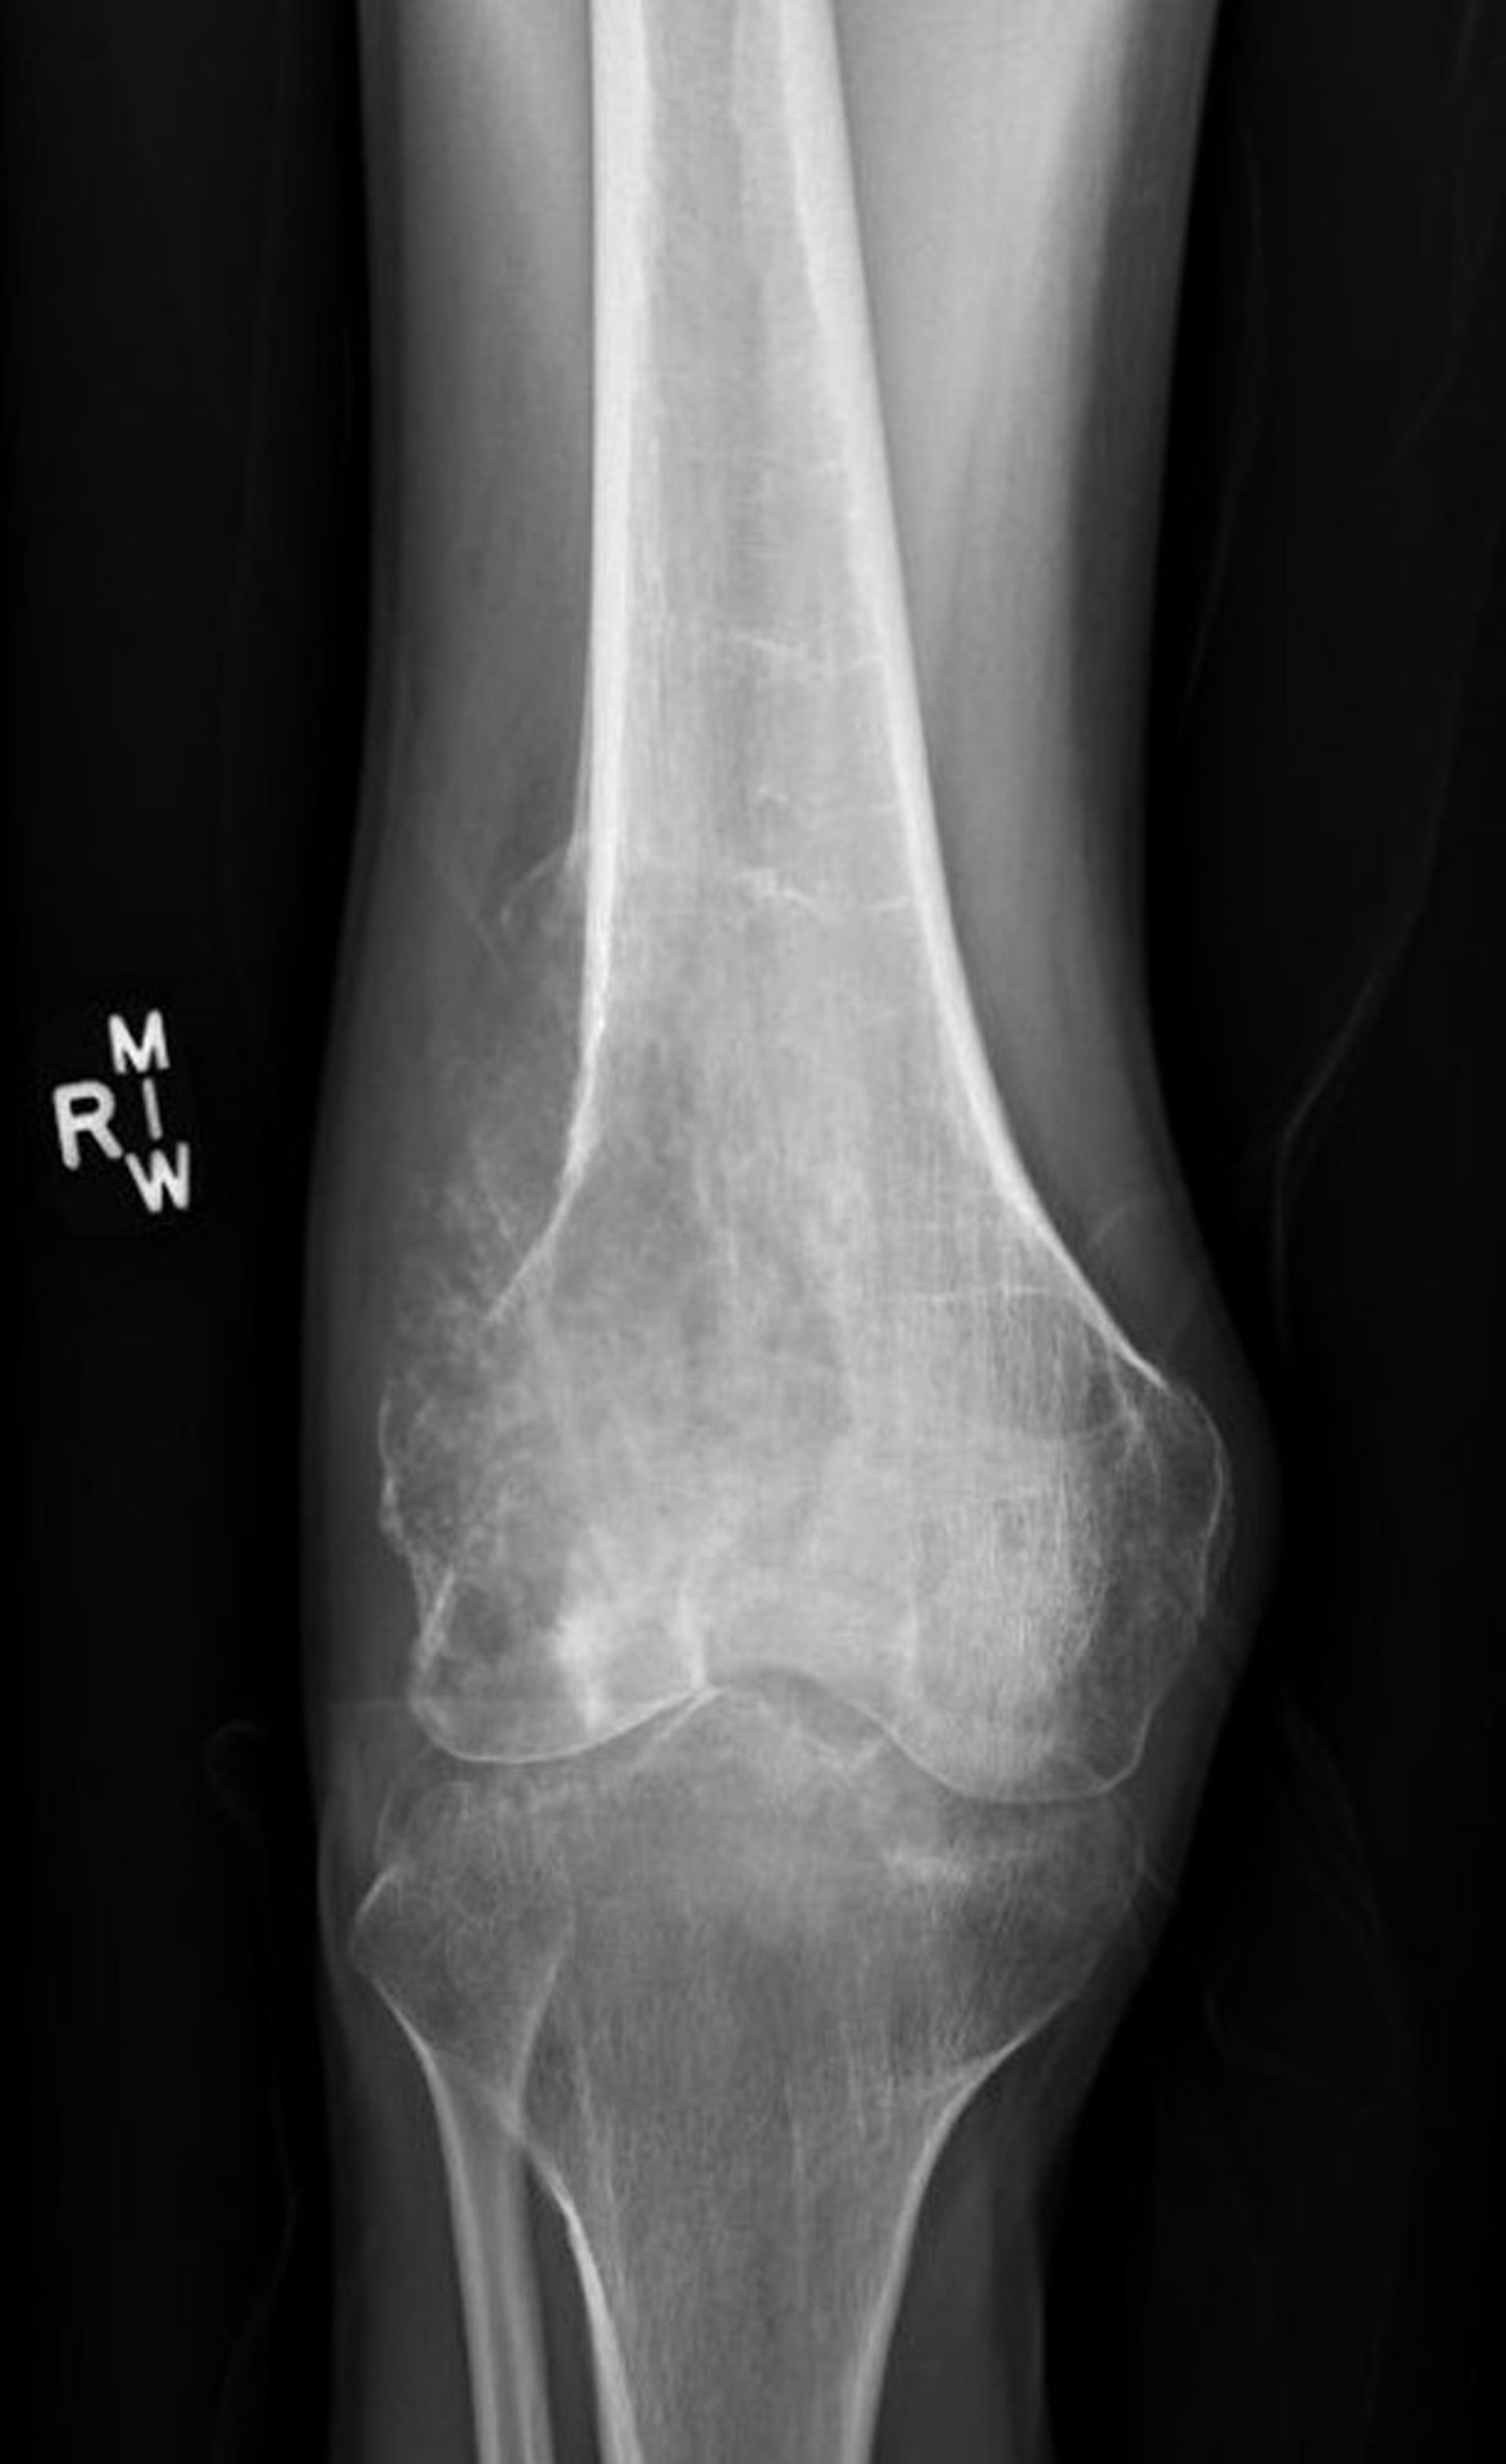

Auf dieser Röntgenaufnahme eines Knies ist ein Osteosarkom im Oberschenkelknochen (Femur) über dem Kniegelenk zu sehen.

Bild mit freundlicher Genehmigung von Dr. med. Lukas Nystrom.